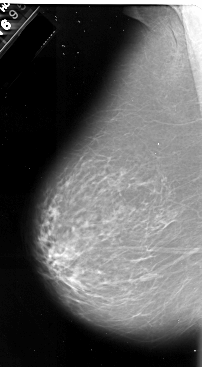

A_1070_1.LEFT_CC

LEFT_CC LINES 6466 PIXELS_PER_LINE 3856 BITS_PER_PIXEL 16 RESOLUTION 42 NON_OVERLAY